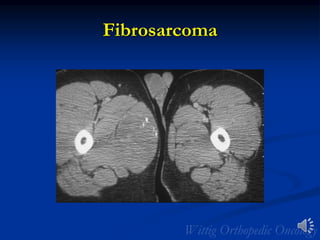

Fibrosarcoma

• Definition: Malignant tumor of fibroblasts that shows no

other evidence of differentiation. The spindle cells are

usually uniform and demonstrate minimal

pleomorphism.

• Rare: 5% of all soft tissue sarcomas

• 40 to 55 years of age; Infantile form <10 yrs of age

• Sites: Intramuscular; rarely in subcutaneous tissue

• Thigh, knee area, buttock

• Arm/shoulder girdle

• Trunk

• Forearms and legs

• Clinical: Painless mass

• Overall 5 yr. survival of 40%

• >60% metastatic rate

• Virtually indistinguishable from MFH on

imaging

Radiology

• MRI

• 2/3 of tumors are intramuscular

• Well defined heterogeneous mass

• Necrosis and hemorrhage are common especially in

higher grade tumors

• Viable areas enhance with contrast; Areas of

significant necrosis and hemorrhage do not enhance